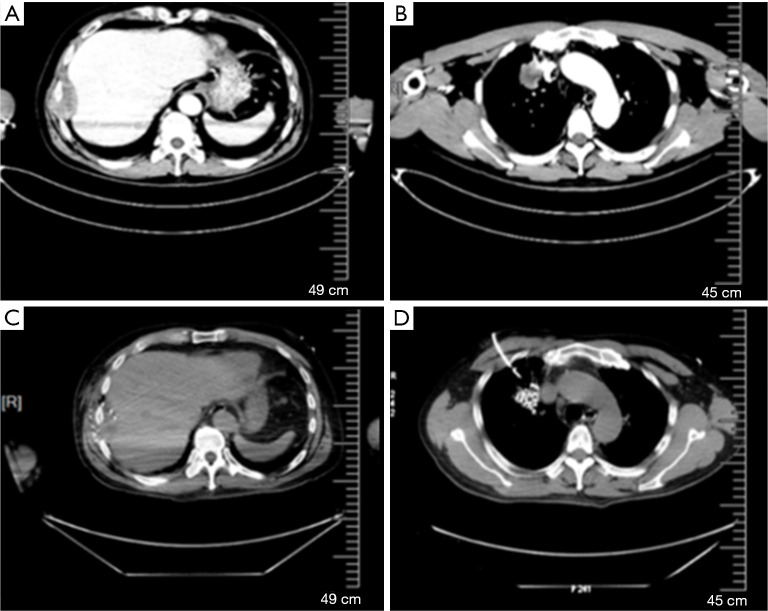

Case description: In this case, we present a 58-year-old male with metastatic pulmonary adenocarcinoma (ADC) who had an EGFR exon 19 mutation and received first-line gefitinib and second-line osimertinib. Biopsy results from different progressive sites confirmed the presence of SCLC in pleural metastatic specimens, while the primary tumor had the EGFR exon 19 mutation and mutations ofPhosphatidylinositol-4,5-bisphosphate 3-kinase catalytic subunit alpha (PIK3CA) andv-Ki-ras2-Kirsten rat sarcoma viral oncogene homolog (KRAS). We utilized an effective combination therapy of permanent radioactive iodine-125 seed implantation (PRISI) as local consolidative therapy (LCT), along with the standard carboplatin-etoposide regimen for SCLC and continued osimertinib. Extracranial tumors were successfully controlled. The patient succumbed to intracranial disease progression without radiotherapy, with an overall survival (OS) of 15 months after SCLC transformation.